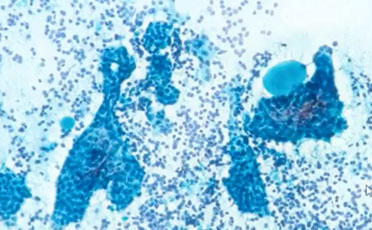

Salivary duct carcinoma, AR and HER2 positive

Salivary Duct Carcinoma

MC in older men; uncommon overall; clinically aggressive

- rsemble comedo ductal carcinoma of the breast

Cyto: Sheets and clusters of large polygonal epithelial cells c obvious malignant features such as large polygonal epithelial cells, irreg nuclear contours c prominent nucleoli

- necrotic background

IHC: AR and HER2 positive

Salivary duct carcinoma, AR and HER2 +